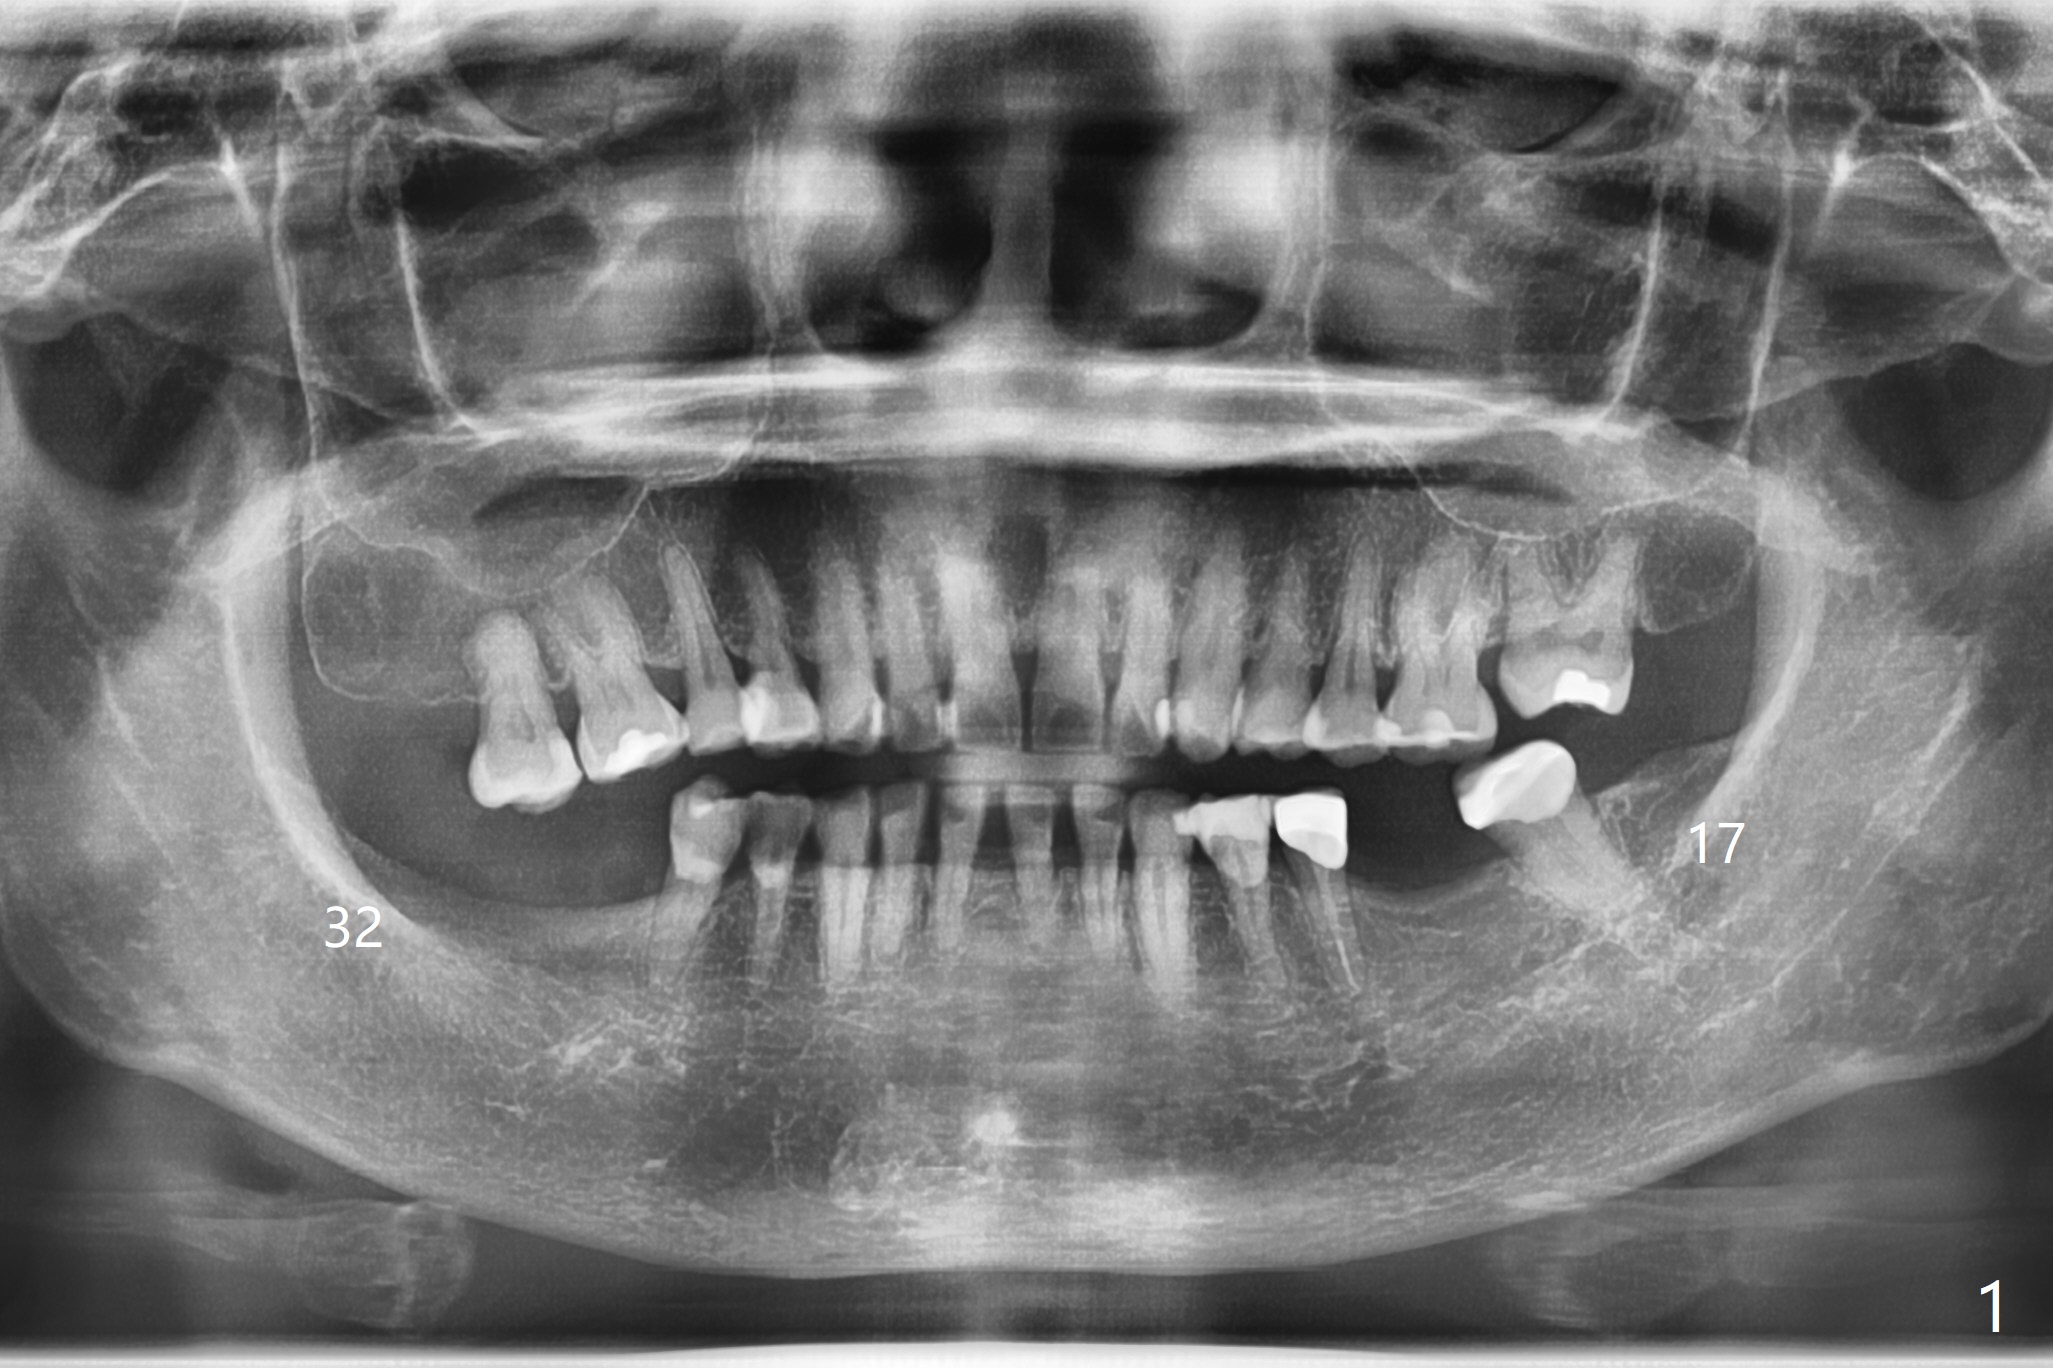

Ten of healthy patients who need extraction of 2 lower 3rd molars simulta-neously will be recruited.  They will enter 2 studies (5 each).  The first study determines whether the osteo-conductive matrix, ß-TCP (beta tricalcium phosphate) promotes bone regeneration.  The 2nd one compares the efficacy of PRF vs. rhPDGF-BB (recombinant human platelet derived growth factor) with using the same osteo-conductive matrix, ß-TCP (beta tricalcium phosphate).  The third study compares cortical allograft with ß-TCP using rhPDGF-BB.   The side (#17 vs. 32) of using the test materials will be randomly chosen.

Panoramic X-ray (full mouth (preop, Fig.1), posterior segment (not shown (reduced radiation); immediately and 3-4 months postop)) will be taken.  The socket dimension (mesiodistal and vertical (height)) will be measured as well as bone density (Fig.2).  In fact it is impossible to measure bone density using panoramic X-ray.  CT should be taken.  The results of the study will reveal whether the combination of rhPDGF-BB and cortical allograft promotes hard tissue healing in 3-4 months.  If there are 2 sockets (mesial and distal), bone density will be recorded twice and average will be obtained for the study.